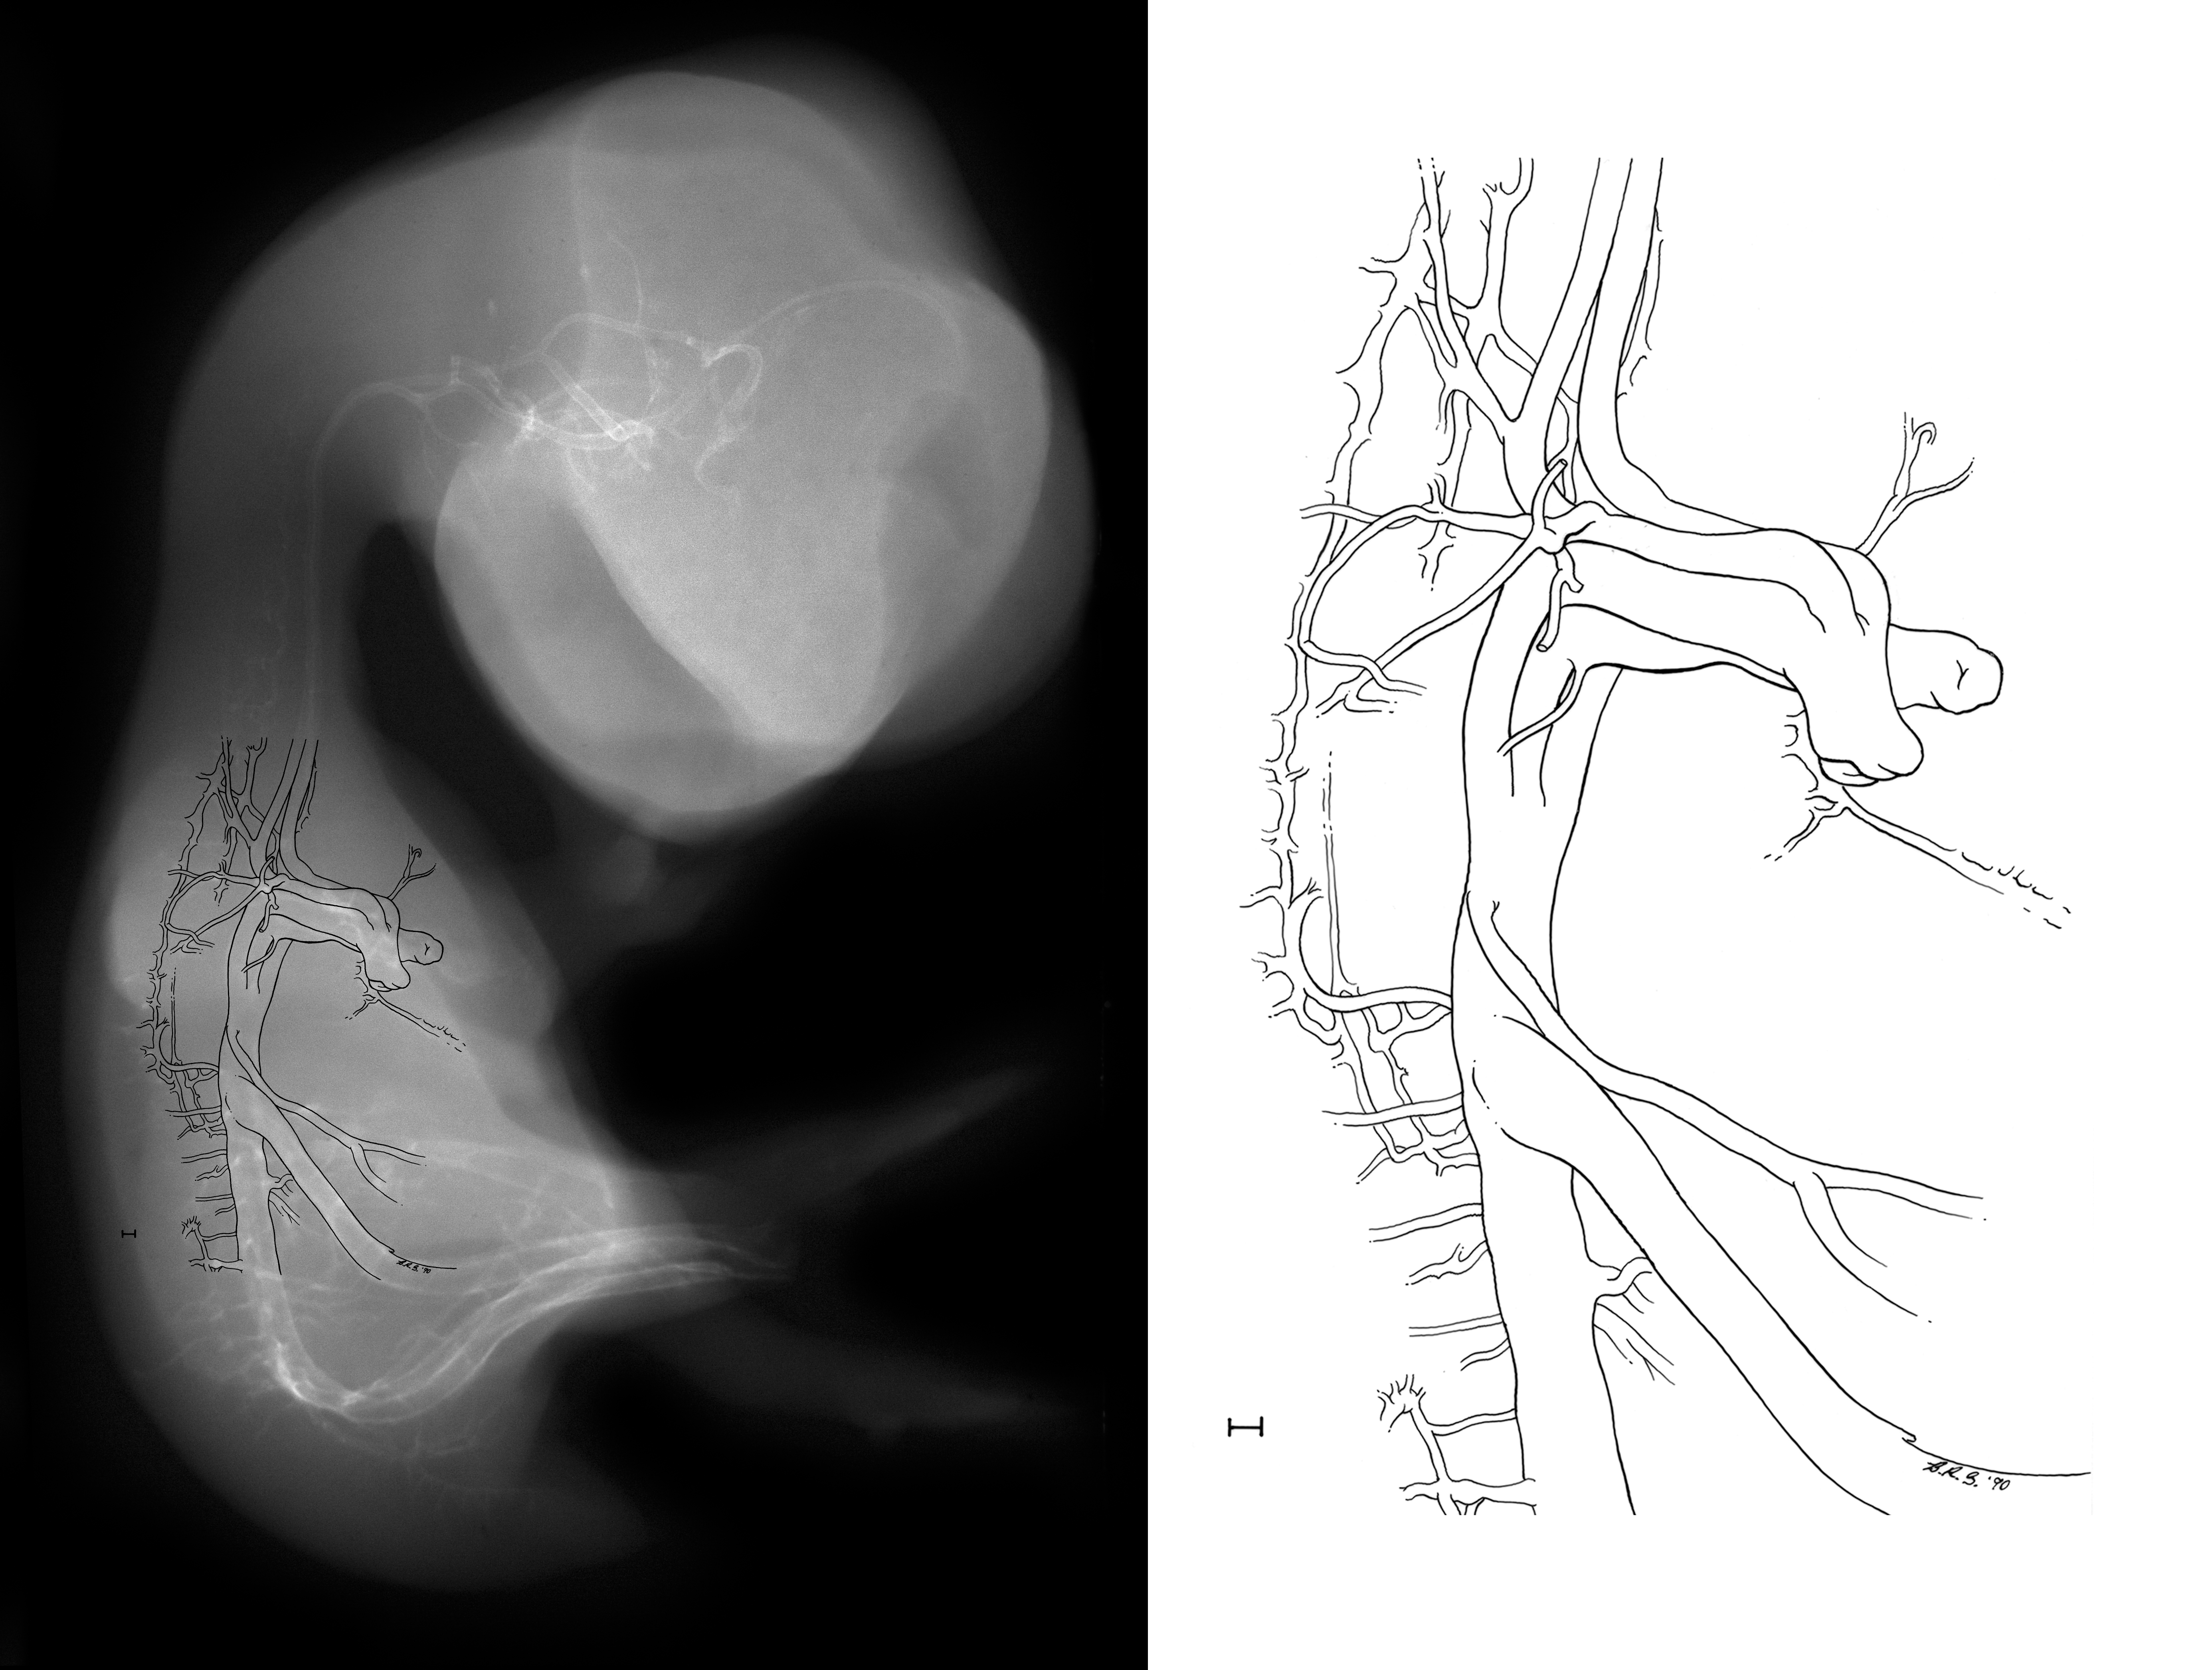

Chick Embryo Microangiography

Hamburger-Hamilton (HH) Stage 35 (approx. 8.5 - 9 days)

Drawing